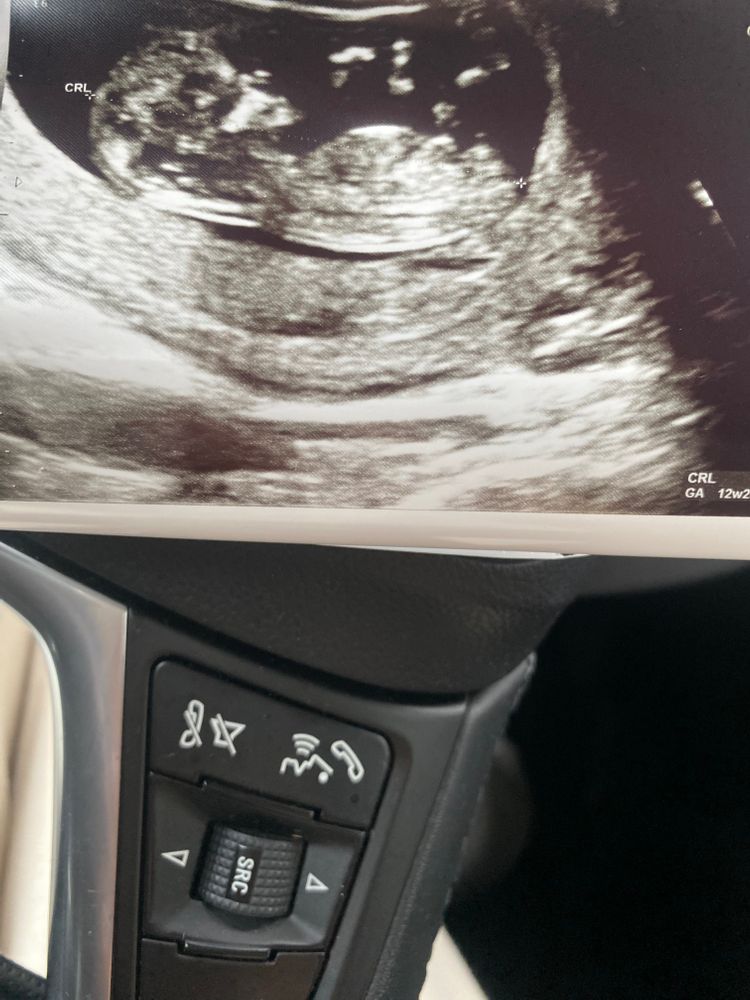

Кого видно на 12.6 неделях 🥰 и какая вероятность ошибки 1 скрининг .

Если то, что я увидела - половой бугорок, то мальчик, т.к. торчит вверх. У девочек он на этом сроке более горизонтально лежит.

По первому фото, если я правильно вижу половой бугорок очень вертикально смотрит, что похоже на мальчика, но качество фото не очень🤷‍♀️

Скорее всего мальчишка.Бугорок не параллельно позвоночнику и приподнят

На мальчика похоже, но не точно🙂

Определяем пол😅 Скрининг 11,6н.